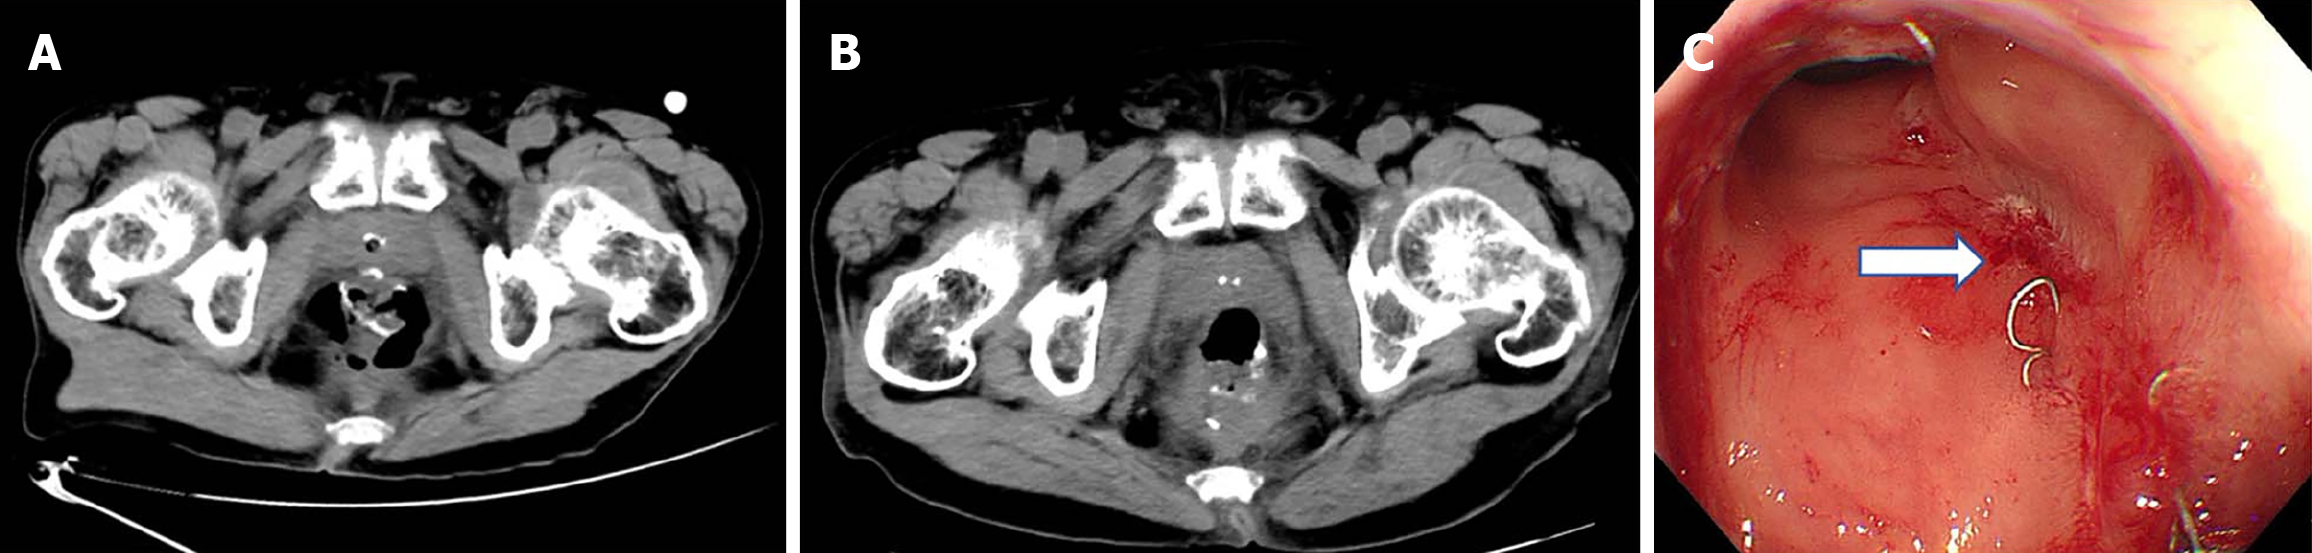

Case 3: After 1 year of follow-up, the anastomotic defect remained unhealed. Pelvic magnetic resonance imaging con

Follow-up visits showed progressive healing of the anastomotic defect. Digital rectal examination approximately 3 months after TROPIS confirmed an intact anastomosis with localized scar formation. Contrast-enhanced magnetic resonance imaging demonstrated no evidence of leakage (Figure 4B), and colonoscopy revealed a smooth and intact anastomosis (Figure 4C). Ileostomy reversal was subsequently performed to restore bowel continuity.